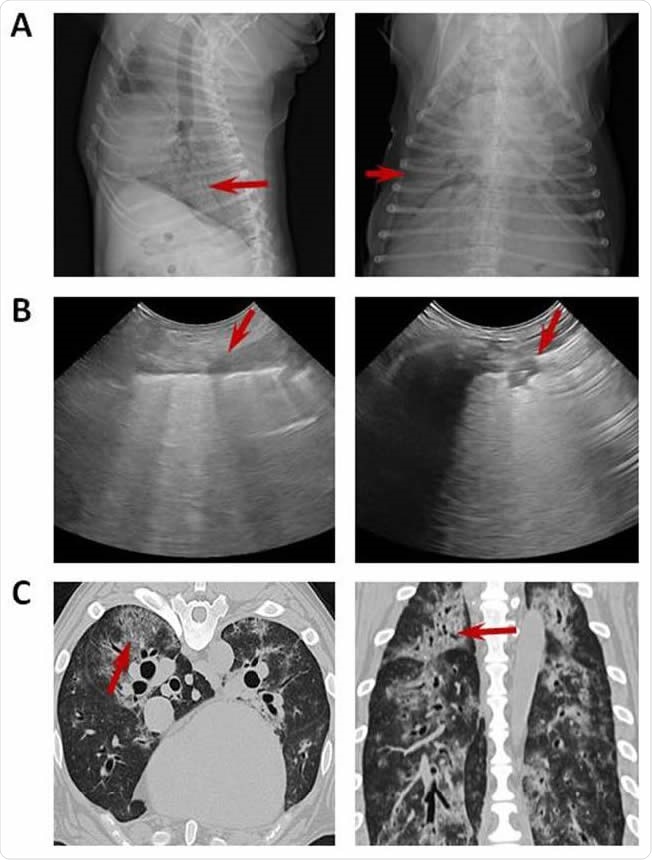

Imaging with chest radiograph, sonographic images and CT. (A) Thoracic radiograph made in right lateral (left) and dorsoventral (right) showing a generalized severe interstitial opacity accentuated in the caudodorsal (arrows). (B) Sonographic images of two patients with severe dyspnea showing a diffused B line (left; arrow) and consolidation focal lesions (right; arrow). (C) Transverse (left) chest CT images showing bilateral focal peripheral ground-glass opacities with intralobular and interlobular smooth septal thickening (arrow); sagital (right) chest CT images showing diffuse opacities with consolidation and bronchial wall thickening (arrow).

All sick dogs had radiological signs of alveolar or interstitial pneumonia. In over a third, generalized lung opacity was present, and in half, a single alveolar focus of infiltration. Ultrasound and CT scans showed bilateral parenchymal abnormalities.